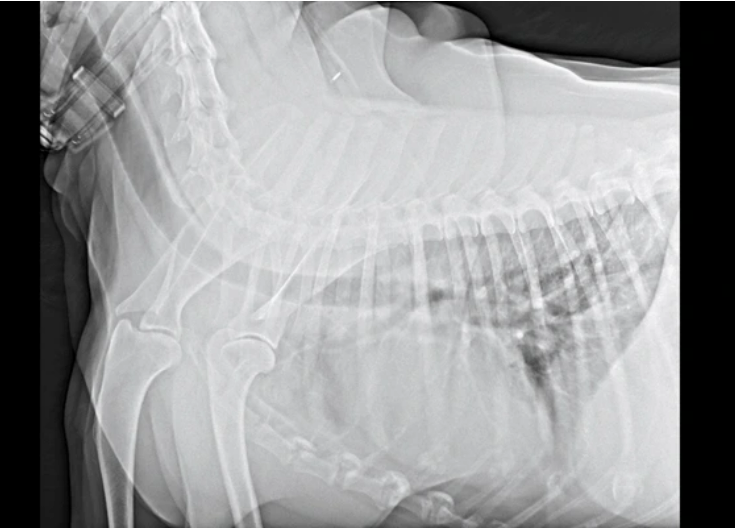

X-ray (엑스레이): 골절이나 관절염의 징후를 확인하는 데 사용됩니다. 그러나 골괴사 초기 단계에서는 X-ray 영상에서 특별한 이상 소견이 나타나지 않는 경우가 많습니다. 질환이 진행되어 뼈의 변화가 나타난 후에야 X-ray에서 확인할 수 있습니다.

MRI (자기공명영상): 골괴사의 조기 진단과 침범 정도를 파악하는 데 가장 민감하고 정확한 방법으로 널리 사용됩니다. MRI는 뼈와 연조직의 상세한 이미지를 제공하여 뼈 손상의 정도를 시각화하고 혈류를 평가하는 데 도움을 줍니다. X-ray로는 확인하기 어려운 초기 변화를 감지할 수 있어, 증상이 미미하더라도 골괴사가 의심되는 경우 필수적인 검사로 간주됩니다.

CT Scan (컴퓨터 단층 촬영): CT 스캔은 뼈의 상세한 단면 이미지를 제공하며, 특히 뼈 함몰 여부를 판단하는 데 유용합니다. 비용이 많이 들고 상당량의 방사선에 노출된다는 단점이 있습니다.

Bone Scan (골 스캔): 방사성 물질을 정맥에 주사한 후, 손상되거나 치유 중인 뼈 부위에 물질이 축적되는 것을 영상으로 확인하는 방법입니다.